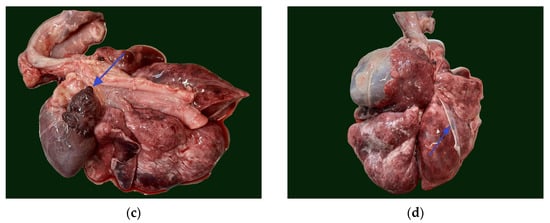

The mitral valve was thickened and nodular and continued with thickened chordae tendineae (Figure 6a). The left atrium presented endocardial regurgitation scars (jet lines), as a consequence of mitral regurgitation. Within the left atrial auricle, a small outpouching structure (5 mm diameter) communicating to the atrial lumen was present (Figure 5c). This structure was identified as an atrial diverticulum within the confines of the pericardium. No signs of left atrial herniation or a pericardial defect were observed. The atrial diverticulum had a smooth interior wall and was completely covered by epicardium. Histologically, the diverticulum retained all three layers of the atrial wall, although it exhibited marked thinning of the myocardium and endocardium, with the thinnest area measuring less than 140 μm (Figure 7a,b).

In addition to the cardiac abnormalities, the evaluation of the thoracic cavity revealed a pulmonary pleural anomaly characterized by an abnormal pleural insertion at the level of the right middle lung lobe. This abnormality was observed as a fibrous, transparent membrane in direct contact with both the thoracic wall and the pulmonary lobe and was not accompanied by significant lung fibrosis (Figure 5d).

Besides all the thoracic findings, within the abdominal cavity an extension of the spleen parenchyma into the tail of pancreas was identified macroscopically (Figure 8), which was confirmed histologically as splenopancreatic fusion (Figure 7d).